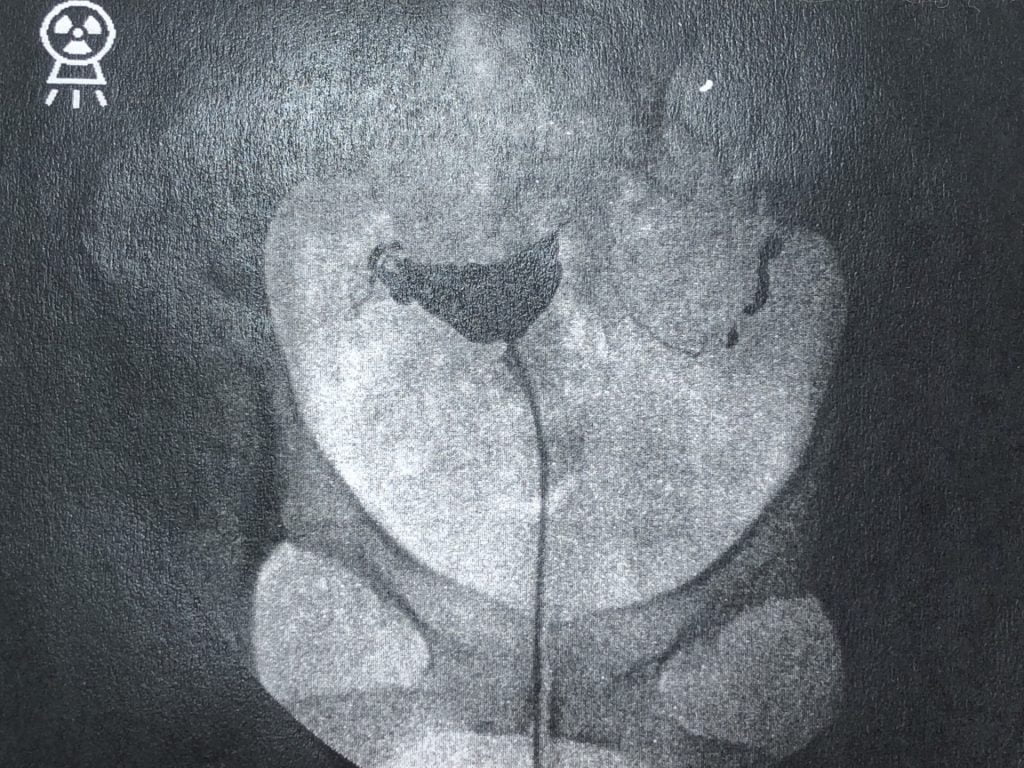

子宮卵管造影検査というのは、子宮の病気や形・卵管が詰まっていないかどうかを調べる子宮のレントゲン検査です!

その後は、すぐにレントゲン写真を撮って、無事に終了となりました!

レントゲンですぐに状態は確認できるので、その後また一旦中待合室で待機し、改めて診察室に呼ばれ、先生から検査結果を教えてもらえました!

私の子宮卵管造影検査の結果としては、問題なし!卵管もしっかり通っていました(^^♪

ということで、自然妊娠の可能性も0ではないということが分かりました。

造影剤を流しても痛みがほとんどなく済んだのは、卵管が通っていたからというのはあるのかもしれませんね。